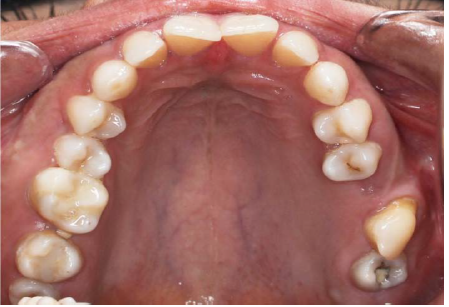

The intraoral examination revealed the transposition of the left maxillary canine that erupted mesial to the third molar (Figure 1). The distal slope of the canine was in contact with the mesial marginal ridge of the lower left third molar. The crown of the transpositioned canine was well-formed with a prominent cingulum (Figure 2).

Figure 2.Occlusal view of the transposed maxillary canine.